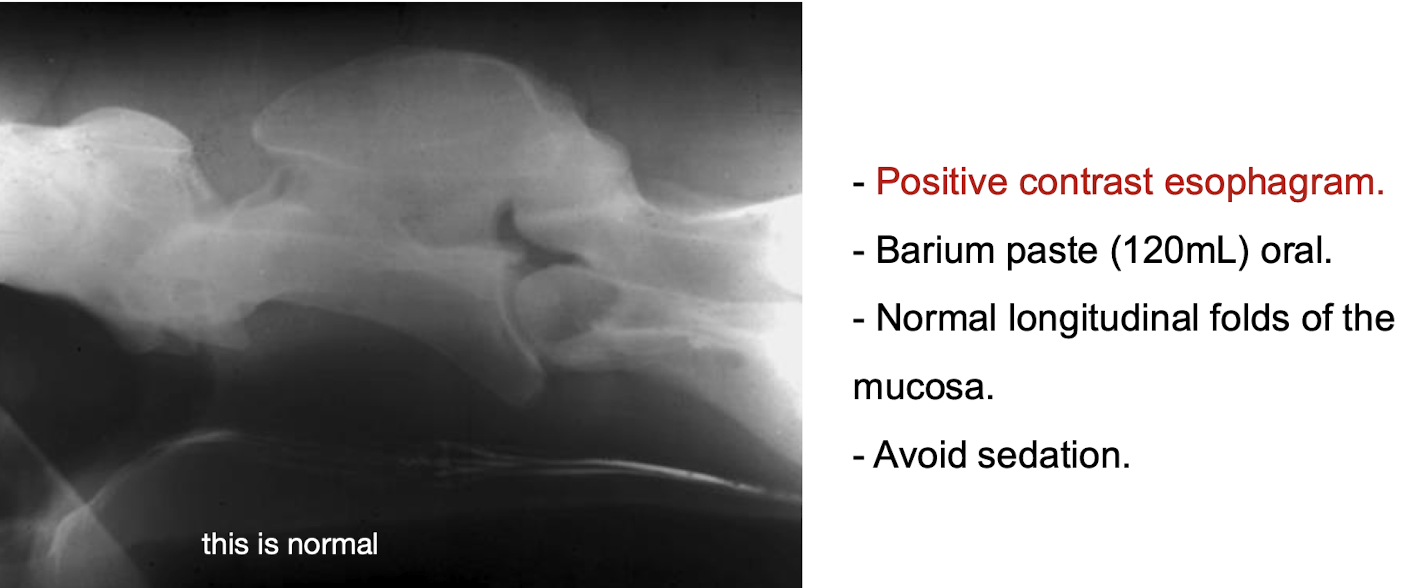

Normal imaging of the neck

What is the purpose of performing a positive contrast esophagram?

To evaluate for esophageal obstructions, strictures, and other lesions.